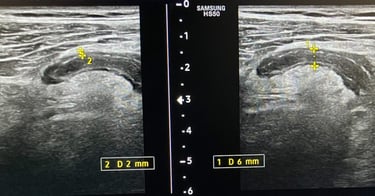

Tumoră cutanată scalp - fără internare, anestezie locală, în ambulator